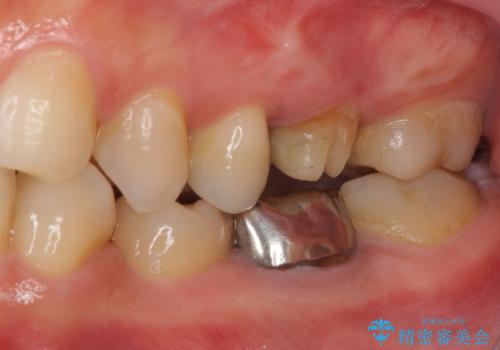

他にも銀歯や欠損となっている歯に対しての治療も希望されたため、補綴治療を行うこととしました。

インプラント治療をきっかけに、銀歯を全てセラミックに替えていきました。